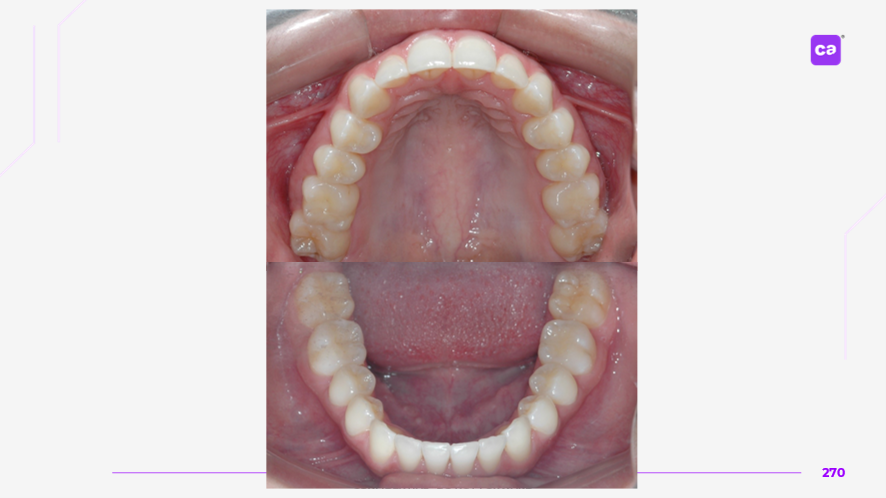

Figuras 3 – Fotos intraorais do caso clínico apresentadas em norma frontal e de perfil:

a) Condição inicial do caso clínico

b) Condição final do caso clínico

Na sequência apresentada, com os registros e comparação das fotos intraorais, observa-se a evolução do caso clínico desde a condição inicial até a finalização do tratamento com a conclusão do uso da série de alinhadores. Os resultados evidenciam a previsibilidade e acurácia do tratamento real em comparação às simulações e ao planejamento virtual inicial.

Observa-se a correção da sobremordida (mordida profunda), com avanço e torque vestibular dos incisivos superiores, juntamente com o nivelamento e alinhamento dentário das arcadas superior e inferior.

Além disso, nota-se o ajuste da linha média dentária superior, garantindo sua coincidência com a linha média inferior, bem como a otimização da curva e da estética do sorriso.